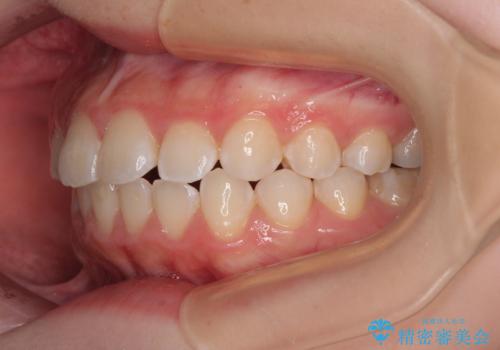

- 上下前歯部のデコボコを気にして来院された患者様です。

叢生は軽度であったため、マウスピースでもワイヤー装置でも対応可能でしたが、マウスピースを長時間使用する自信がないとのことでワイヤー装置にて矯正治療を行うこととしました。

叢生が軽度であったため、僅か半年で装置を除去することができました。